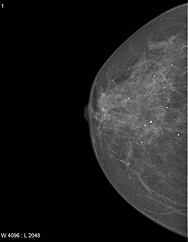

CC Right

Right CC Sample

CC Right Grad-CAM